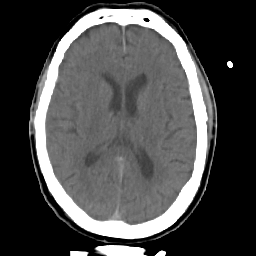

Meningioma: Roentgen-ray CT #2 -- Slice #11

[Home][Help][Clinical] Slice 11